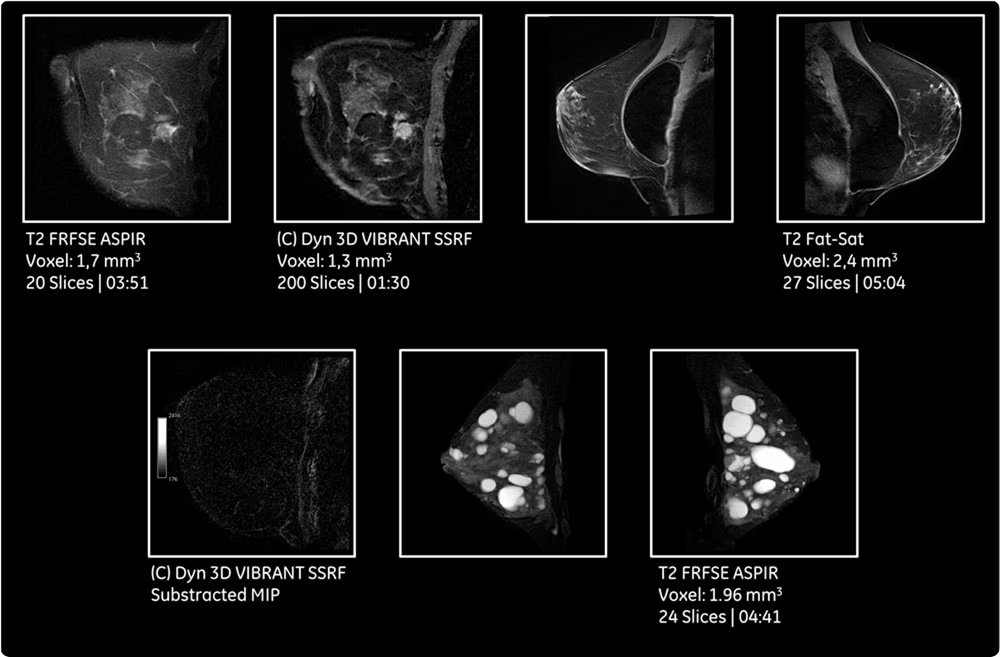

| Динамические контрастные исследования | Серийное сканирование после введения контрастного препарата для оценки васкуляризации и характеристик образований. |

| Специализированные протоколы для позвоночника и суставов | Высокодетализированные последовательности для оценки межпозвонковых дисков, суставных поверхностей, связочного аппарата и костного мозга. |